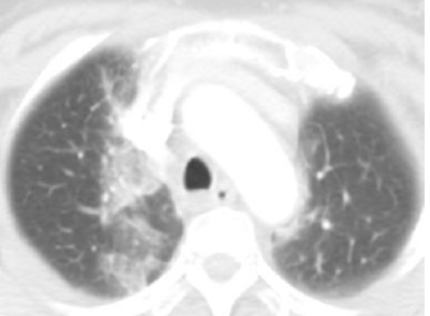

Bgr41Qgrm9eecp6p.jpg yBsczorQ4sRNn4Qo.jpg

放射野内条索影